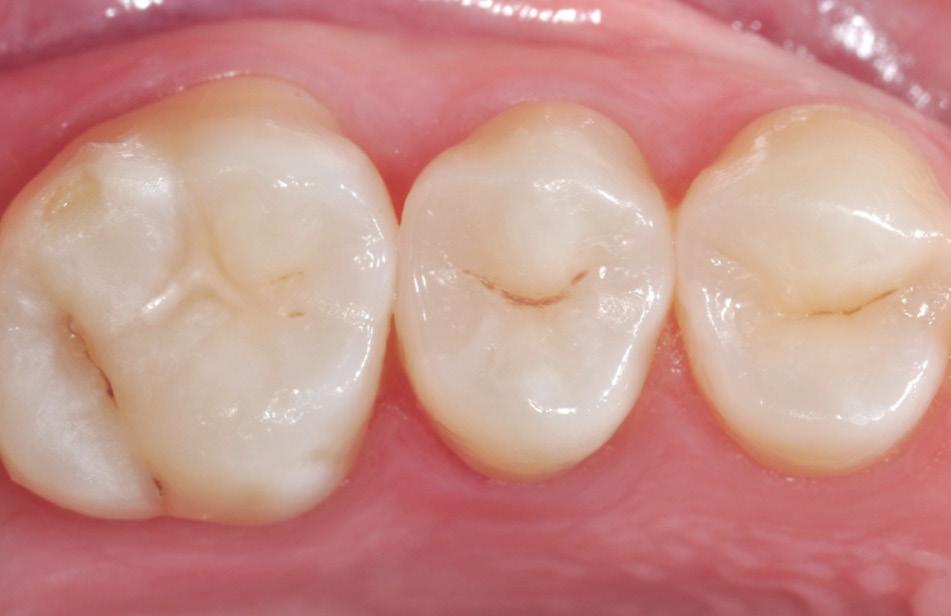

Fig. 9: After removal of the matrix band, the composite was cured for 10 seconds on both the buccal and lingual surface.* Fig. 10: After finishing and pre-polishing, the 3M™ Sof-Lex™ Diamond Polishing System on moist surface was used to create a high gloss polish.

Fig. 11: Final outcome using 3M™ Filtek™ One Bulk Fill Restorative.